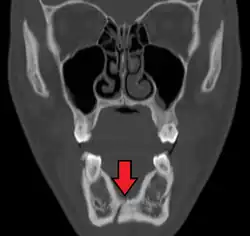

Traditionally, plain films of the mandible would be exposed but had lower sensitivity and specificity owing to overlap of structures. Views included AP (for parasymphsis), lateral oblique (body, ramus, angle, coronoid process) and Towne's (condyle) views. Condylar fractures can be especially difficult to identify, depending on the direction of condylar displacement or dislocation so multiple views of it are usually examined with two views at perpendicular angles.[11]

Panoramic radiography

Panoramic radiographs are tomograms where the mandible is in the focal trough and show a flat image of the mandible. Because the curve of the mandible appears in a 2-dimensional image, fractures are easier to spot leading to an accuracy similar to CT except in the condyle region. In addition, broken, missing or malaligned teeth can often be appreciated on a panoramic image which is frequently lost in plain films. Medial/lateral displacement of the fracture segments and especially the condyle are difficult to gauge so the view is sometimes augmented with plain film radiography or computed tomography for more complex mandible fractures.

Computed tomography

Computed tomography is the most sensitive and specific of the imaging techniques. The facial bones can be visualized as slices through the skeletal in either the axial, coronal or sagittal planes. Images can be reconstructed into a 3-dimensional view, to give a better sense of the displacement of various fragments. 3D reconstruction, however, can mask smaller fractures owing to volume averaging, scatter artifact and surrounding structures simply blocking the view of underlying areas.

Research has shown that panoramic radiography is similar to computed tomography in its diagnostic accuracy for mandible fractures and both are more accurate than plain film radiograph.[12] The indications to use CT for mandible fracture vary by region, but it does not seem to add to diagnosis or treatment planning except for comminuted or avulsive type fractures,[13] although, there is better clinician agreement on the location and absence of fractures with CT compared to panoramic radiography.[14]

Panoramic radiograph of a simple mandible fracture of the right mandibular body, minimally displaced. Note that the teeth to the left of the fracture do not touch -